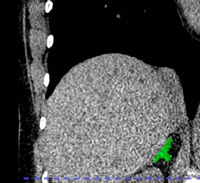

Lead author of the new study, Dr. Elena Ghotbi, developed and trained a deep learning model to measure adrenal gland volume on existing CT scans.

(Elena Ghotbi, M.D., and RSNA via SWNS)

The team applied their deep learning model to the CT scans to segment and calculate the volume of the adrenal glands.